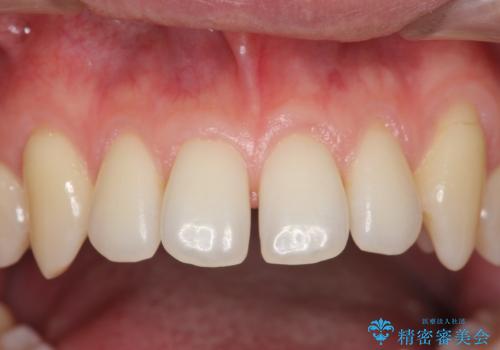

オールセラミッククラウンも選択肢としてあげられましたが、歯の表側のみを削るラミネートベニア修復を選択されました。

裏側の保定装置も外さずに済みました。

今回は裏側の保定装置はそのままで、歯を削る量を最小限にしてベニア修復しました。